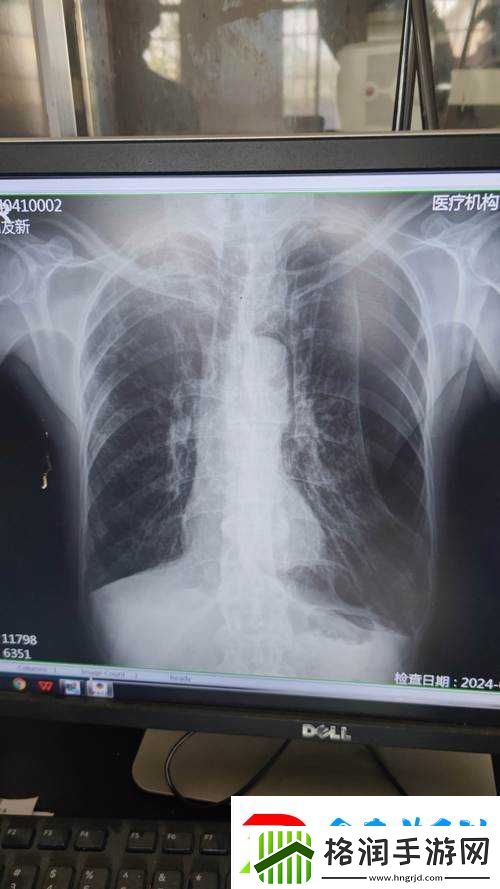

让我们来看看胸片 100%曝光下的图像。这些图像通常呈现出人体内部的骨骼、肺部和其他组织的细节。当我们仔细观察这些图像时,会发现一些不寻常的现象。例如,在某些胸片中,我们可以看到肺部呈现出一种暗淡的红色,这可能是由于肺部感染或其他疾病引起的。在其他胸片中,我们可以看到肺部呈现出一种强烈的红色,这可能是由于情绪激动或其他原因引起的。

接下来,让我们来探讨胸片 100%曝光下愤怒的情绪直观呈现。当我们处于愤怒情绪时,身体会释放出一系列的生理反应,如心跳加快、血压升高、呼吸急促等。这些生理反应会影响我们的身体和心理状态。在胸片 100%曝光下,我们可以看到这些生理反应在肺部的表现。例如,在愤怒情绪下,肺部的血管会扩张,肺部的颜色会变得更加鲜艳,这可能是由于血液供应增加引起的。

胸片 100%曝光下愤怒的情绪直观呈现还可以通过其他方式表现出来。例如,在某些胸片中,我们可以看到肺部的纹理变得更加混乱,这可能是由于情绪激动引起的肺部肌肉紧张引起的。在其他胸片中,我们可以看到肺部的形状发生变化,这可能是由于情绪激动引起的呼吸方式改变引起的。